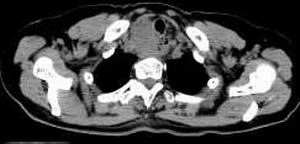

女,61岁,吞咽困难(包括开水)已久。

食道中上段癌并锁骨上窝淋巴结转移.

1、同意食道上段ca併淋巴结转移。

食道中上段中分化鳞癌伴锁骨上淋巴结转移